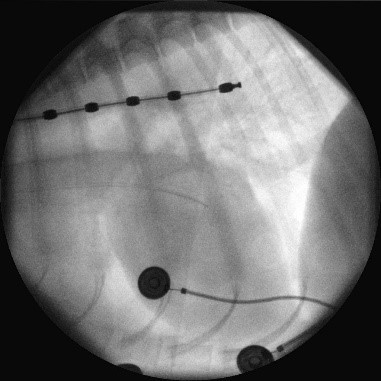

一時ペーシング療法(経食道法、径頸静脈法)

不整脈や心不全の動物を治療している途中で他の病気での手術が必要になる場合があります(骨折、腫瘍、子宮蓄膿症等)。

問題になるのは麻酔による心機能の低下や停止です。

術前の心機能評価を確認いたします。

加えて、心機能低下を未然に防ぐために一時的に体外式ペースメーカーにて心臓の動きをサポートする方法です。

食道や頸静脈にカテーテルを刺して心臓を電気刺激します。

当院では頸静脈ペーシングをお勧めしています。

カテーテル刺入から2-3分でペーシングを開始、術後麻酔終了時又はICU離脱時に抜去いたします。

PCで心拍数を維持するだけではなく拍出量も補助できます。